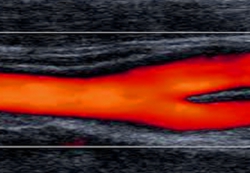

メタボリックシンドロームの認識普及に代表されるように動脈硬化の評価は最も注目されています。

特に頸動脈や下肢血管を非侵襲的に評価出来る血管超音波はゴールデンスタンダードとなっています。更に透析患者などのバスキュラーアクセスや腎動脈評価、下肢静脈瘤など...血管超音波は注目度が高いです。